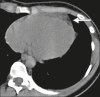

Epipericardial fat necrosis: increasing the rate of diagnosis by disseminating knowledge within a single institution